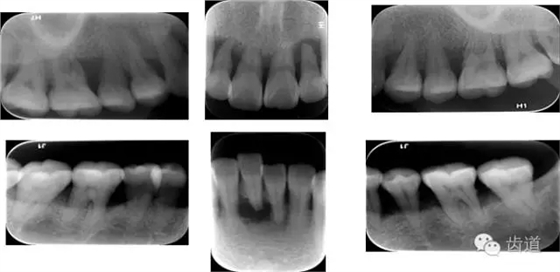

6、輔助檢查

X線:根尖片、曲面斷層片(牙槽嵴頂,水平垂直吸收,程度)